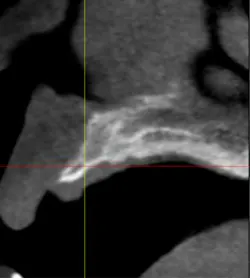

A 43-year-old female with a noncontributory medical history taking no medication and having no known food/drug allergies presented to my general dental office with a chief complaint of having “loose teeth with an underbite.” Clinically, she had generalized, moderate, chronic periodontal disease and was missing teeth Nos. 8 through 10. She had a Class III malocclusion with pathologic flaring of her remaining anterior teeth. She had both vertical and horizontal tissue loss in the No. 8 through 10 region. The patient wore a transitional partial denture to replace the anterior missing teeth that was placed in edge-to-edge occlusion by her previous dentist. (Fig. 1) She did not like having a removable prosthetic and desired a fixed option in the form of implants to replace her missing teeth. I sent her to the periodontist for a periodontal consult for her remaining dentition and dental implants to replace her missing front teeth.